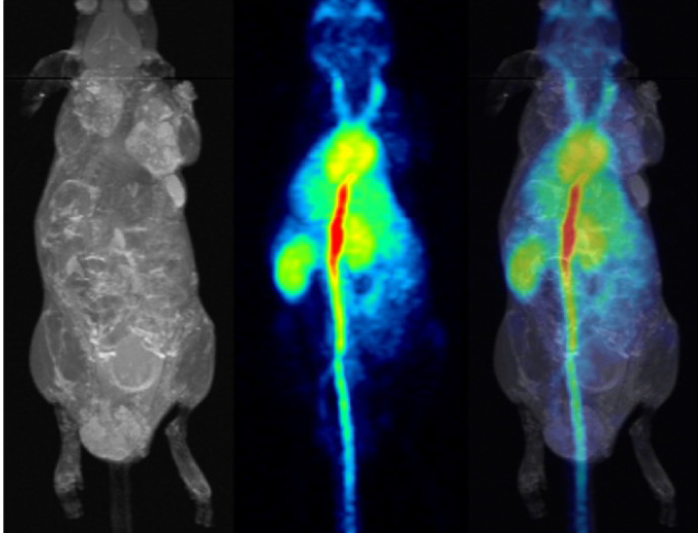

pmod’s tools provide comprehensive workflows for post-processing and quantification of imaging data for fundamental oncology research, development of radiotracers and theranostics, and in clinical research studies. Imaging scientists can trust pmod to reproducibly read their data, interpret the meta-data/units and help users calculate statistics such as SUV for their studies and publications.

For treatment evaluation and theranostic development

• Multimodality segmentation tools – comprehensive semi-automated and manual tools for precision and reproducibility

• Full access to metadata – ensure accurate calculation of Standard Uptake Value and other key statistics

• Flexible switching between 3D and 4D datasets – direct output of time activity curves

• Pipeline processing – leverage pmod’s built-in Data Management System to set up processing batches to power your large studies